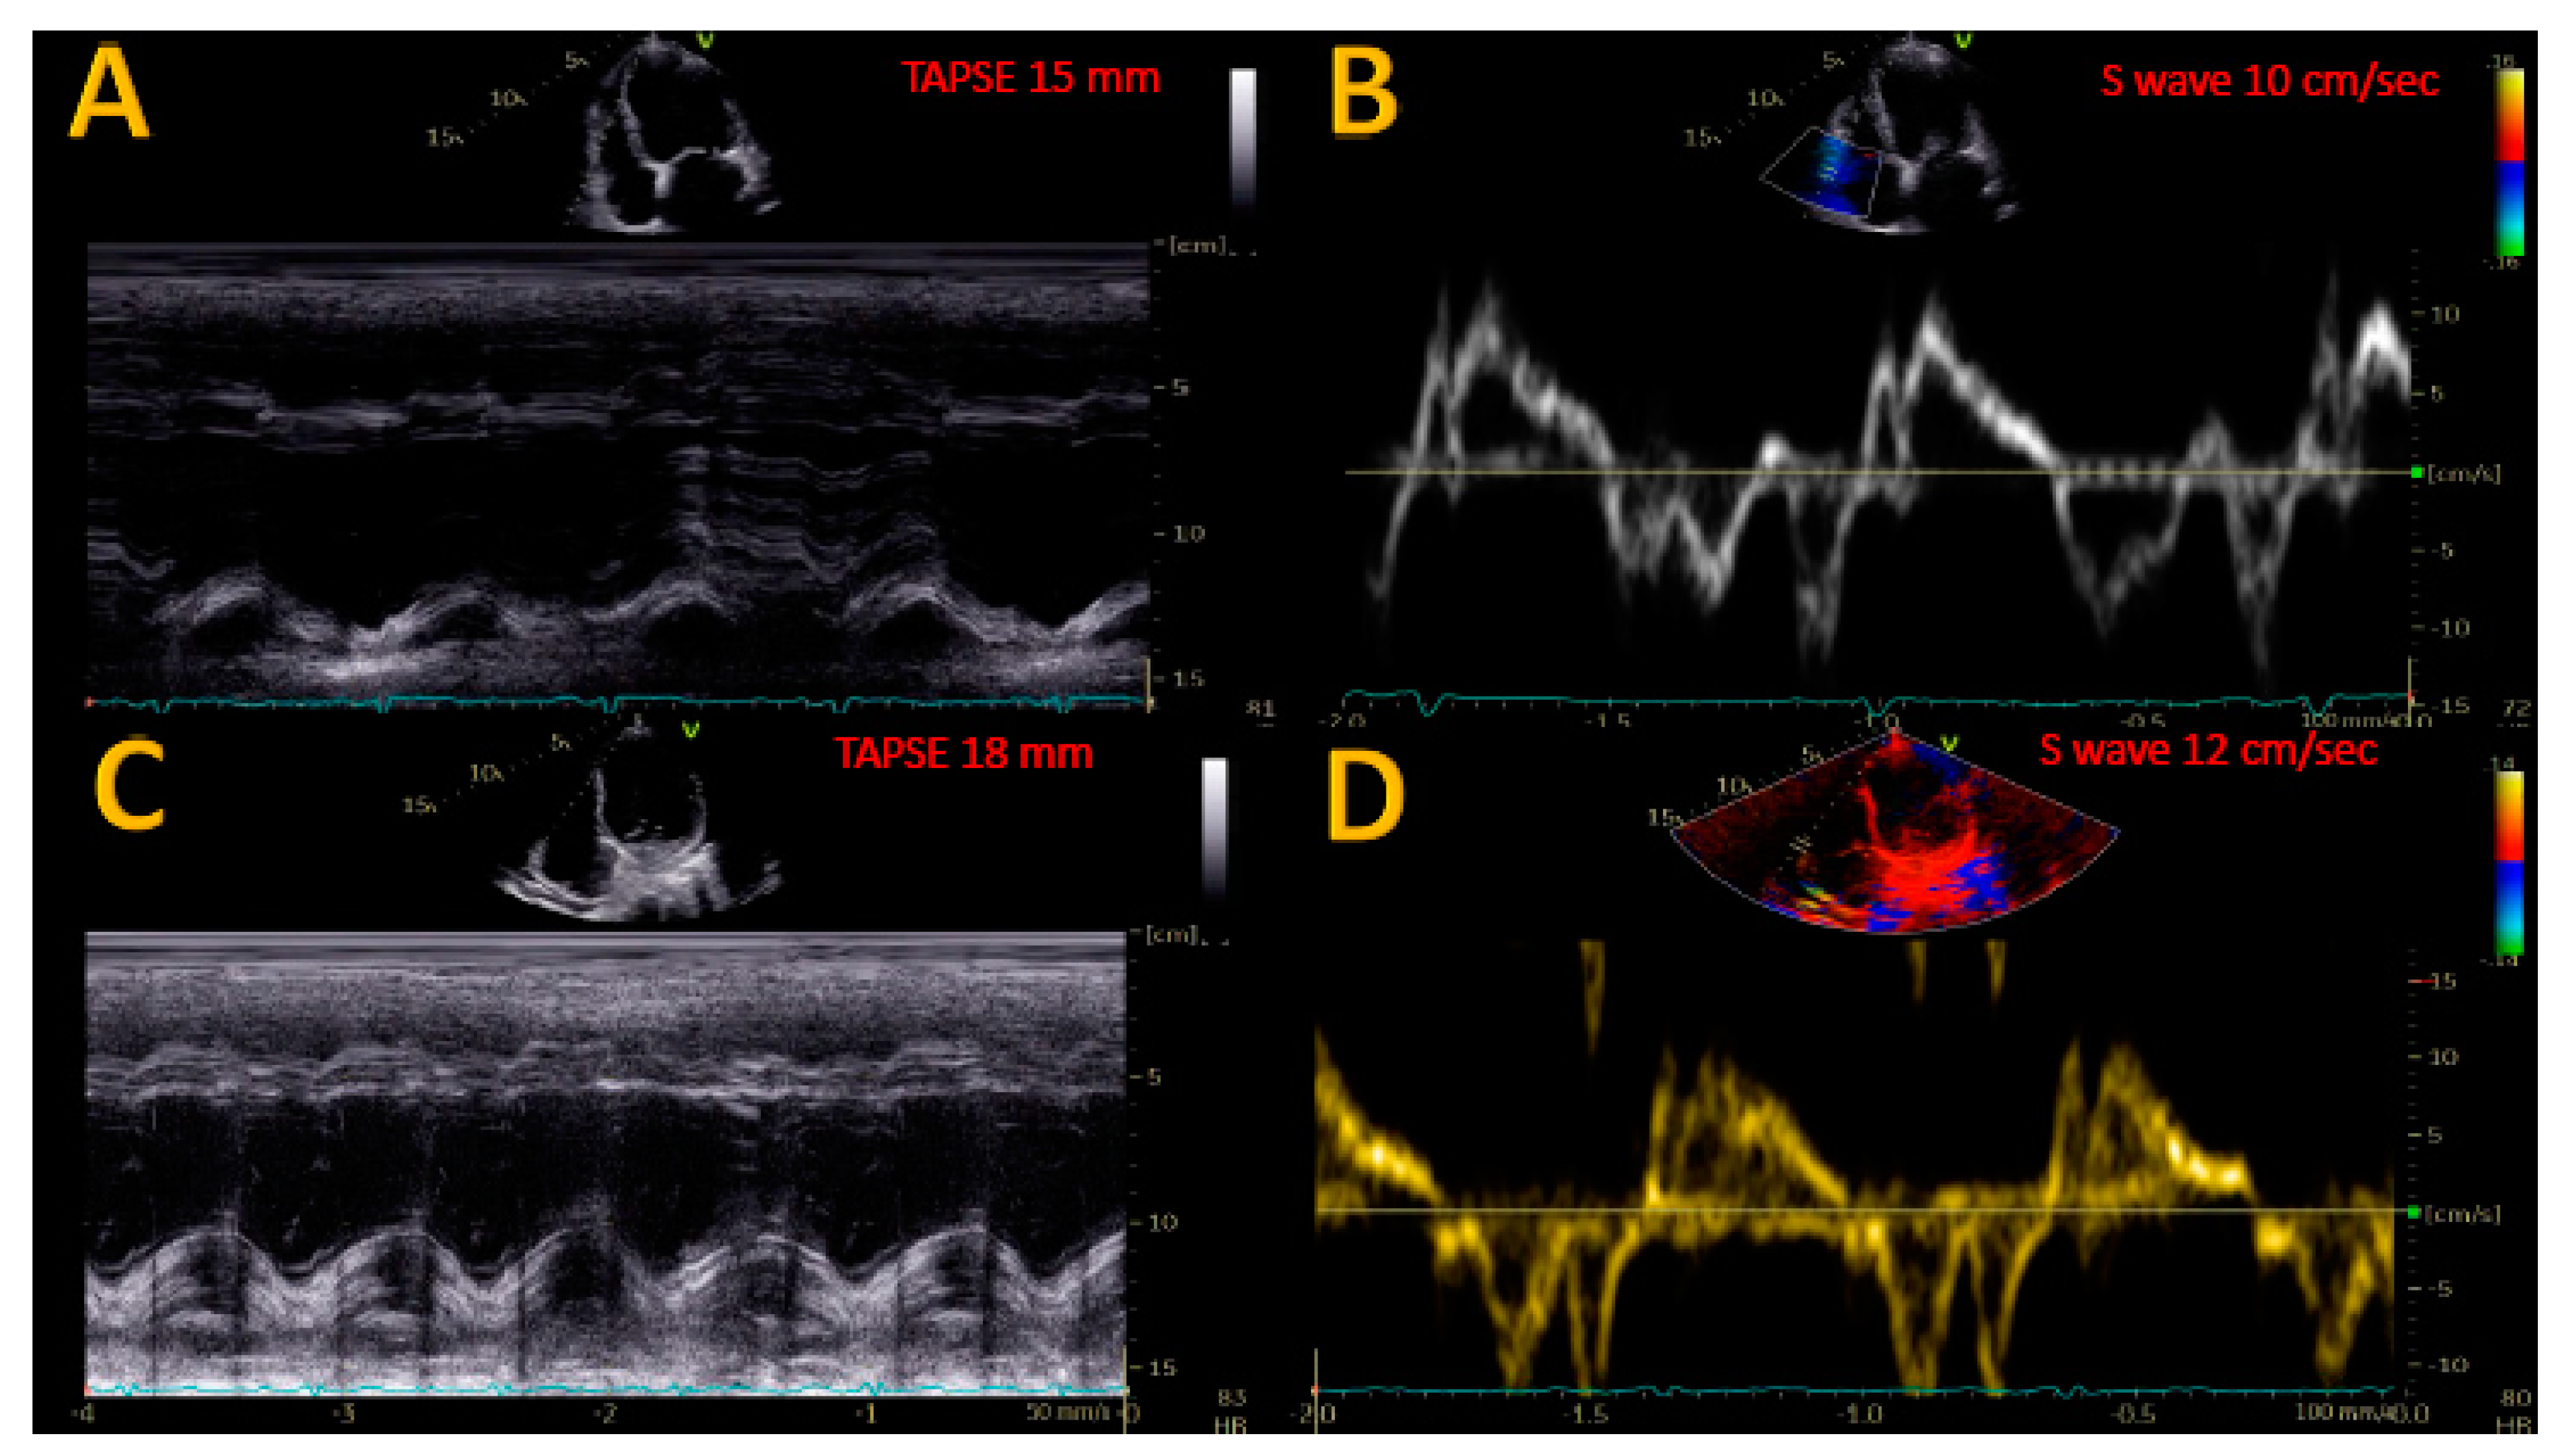

| TAPSE (mm) | 16.6 ± 4.2 | 18.5 ± 3.6 | <0.05 |

| S wave (cm/s) | 10.1 ± 1.8 | 11.3 ± 1.4 | <0.05 |